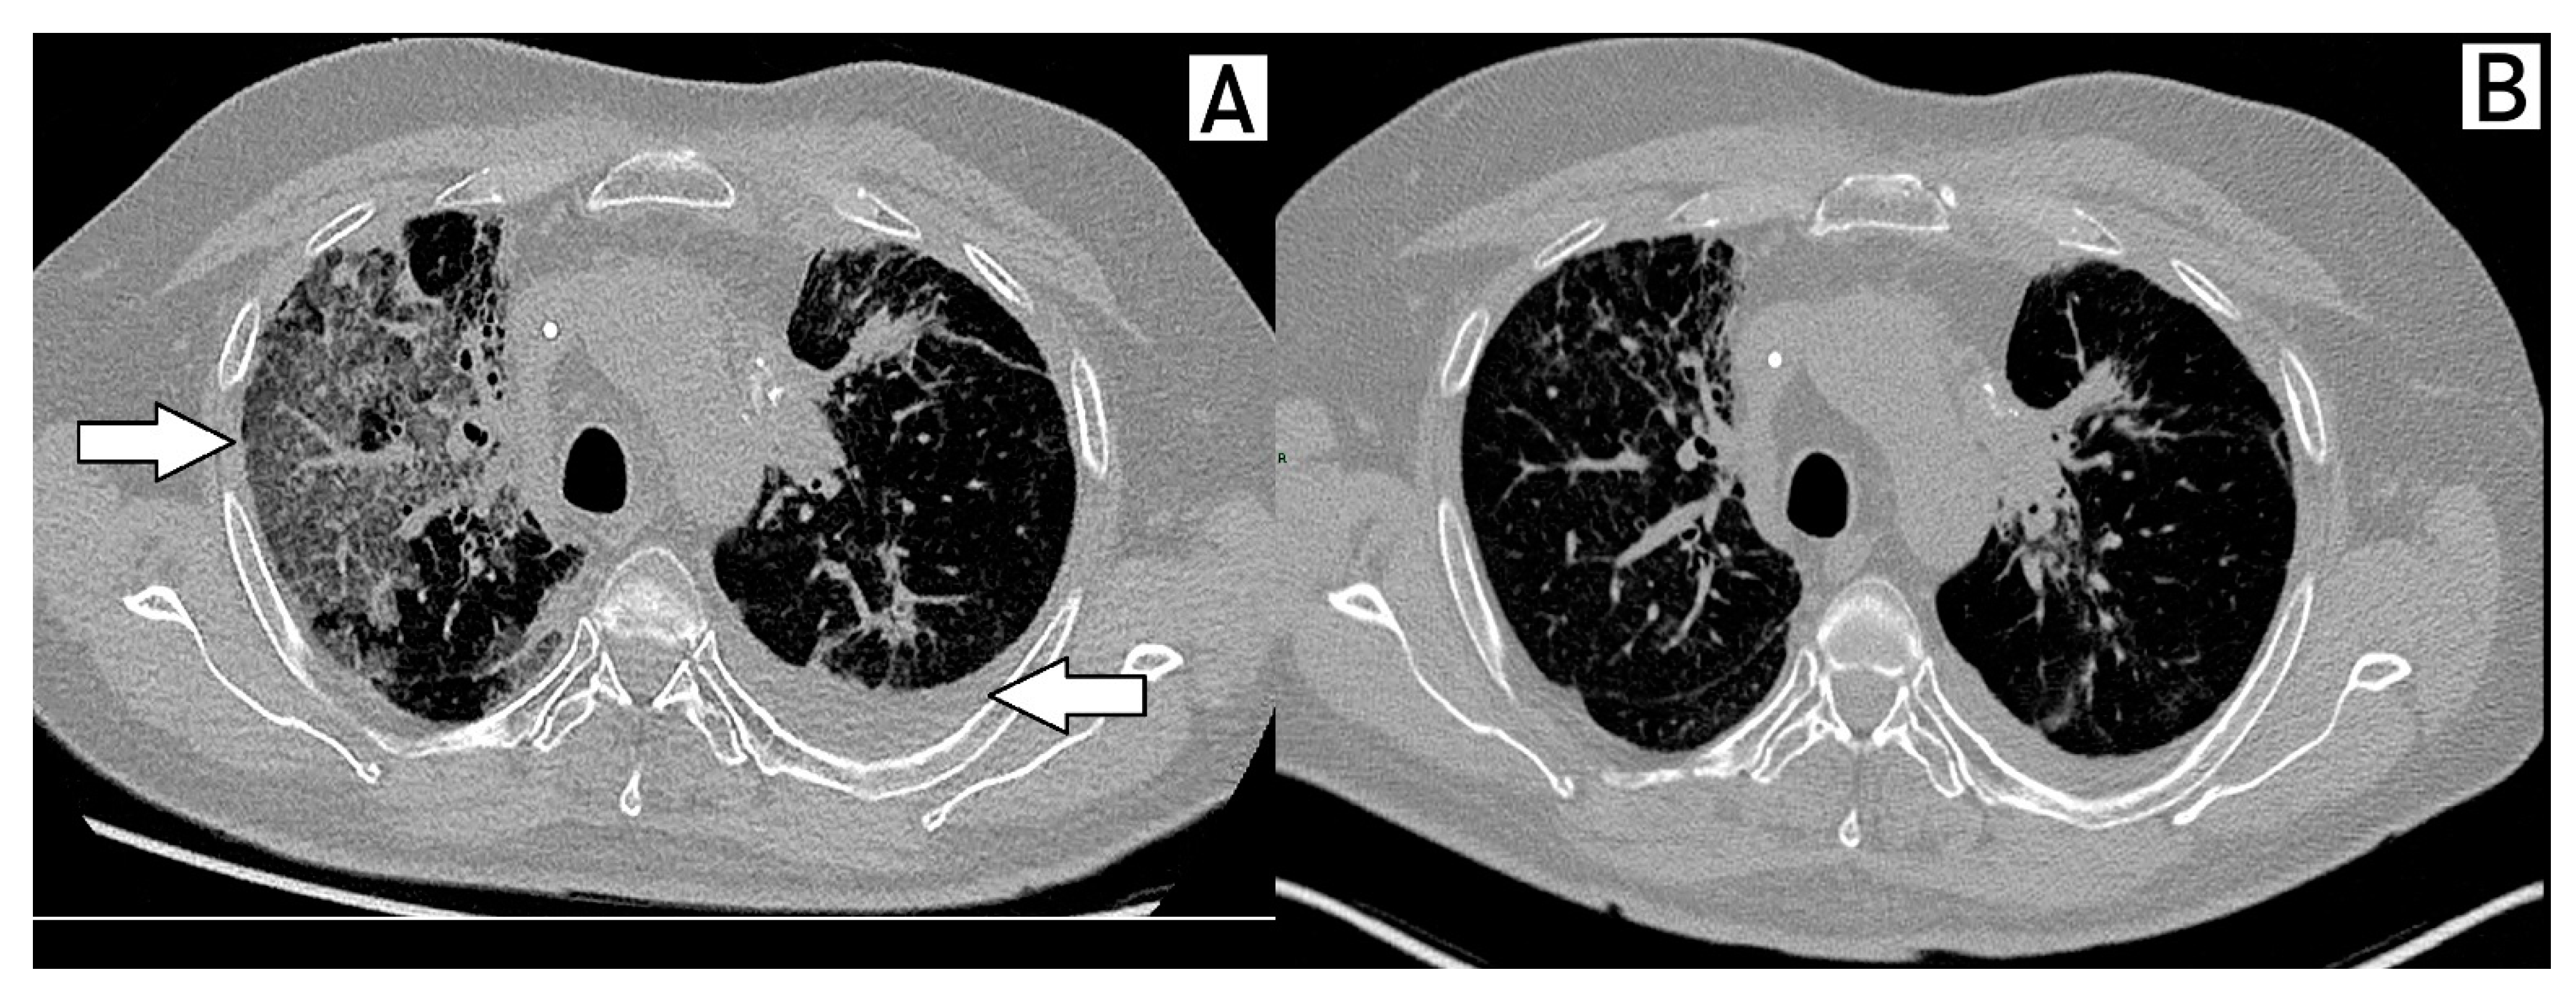

Treatment was maintained until March 2021, when the patient developed dyspnea and respiratory failure secondary to acute pneumonitis requiring orotracheal intubation. High-resolution CT and bronchoalveolar lavage were performed. Grade 4 pneumonitis related to Abemaciclib was considered the most likely diagnosis after the exclusion of infection and disease-related complications. He eventually improved with corticosteroid and Abemaciclib suspension (Figure 3).

Figure 3.

Pneumonitis associated with abemaciclib. Arrows in the figure shows ground-glass opacities, suggesting pneumonitis of the right lung and pleural effusion in the left lung (A). Resolution of pneumonitis 3 months after drug discontinuation (B).